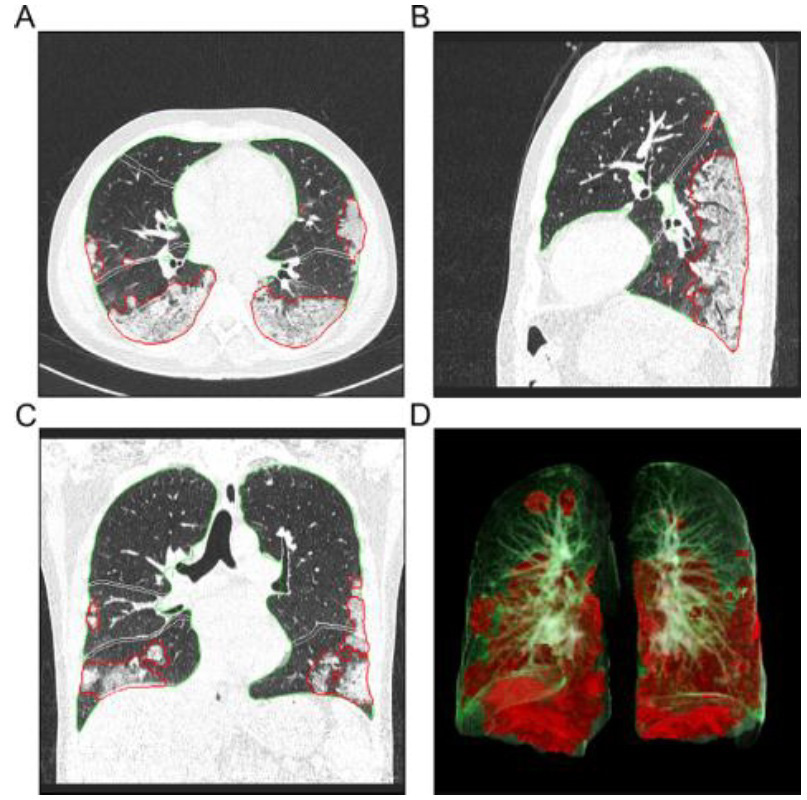

Figure 1: CT images showing postprocessing analysis and quantification results of the evaluated AI-driven software prototype [13].

figure 1